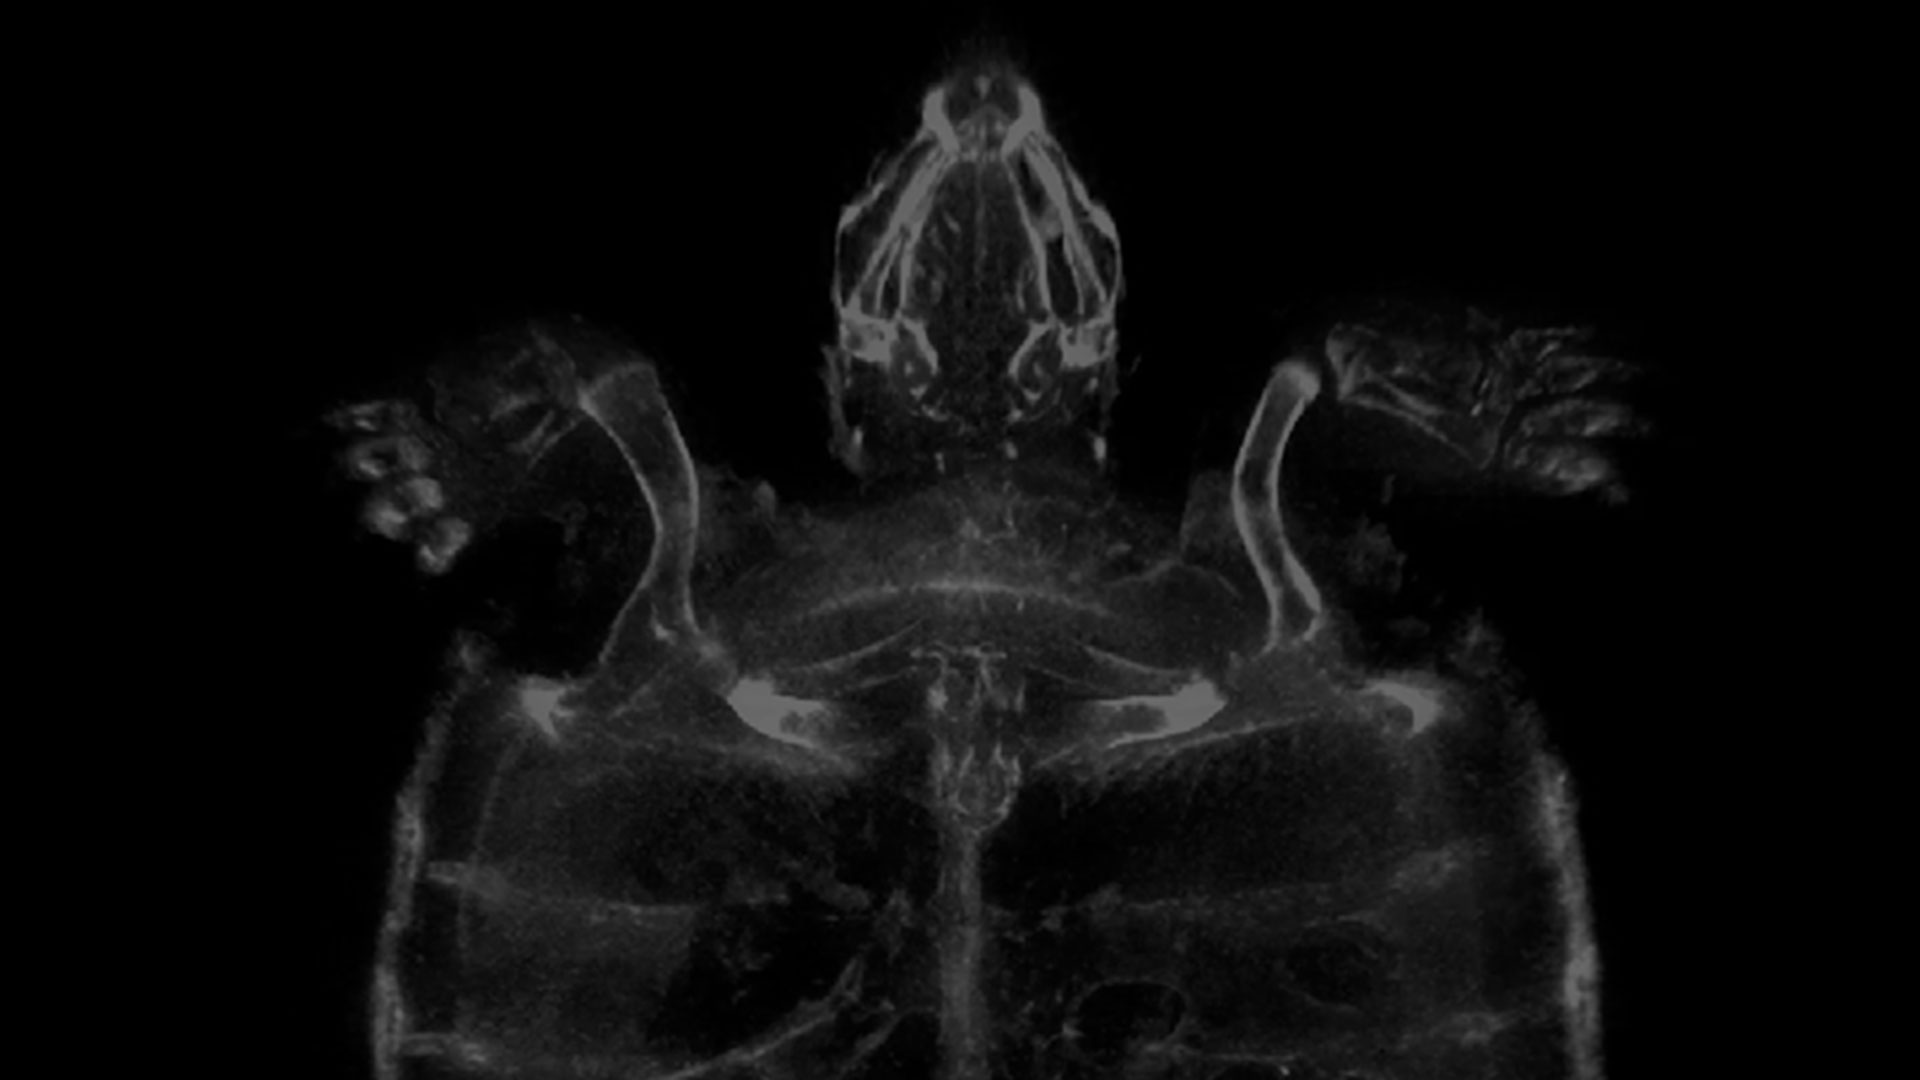

With the development of our Veterinary 3D Imaging Product quickly progressing, interest from the industry is really picking up and we were delighted when the Vet Times approached Dr. Steve Wells (Vice President of Technology) to talk about the product and the recent trials we have been doing with Bicester Vets (with thanks to Jason Williams, MRCVS) and Chipping Norton Veterinary Hospital (with thanks to Martin Whitehead, MRCVS).